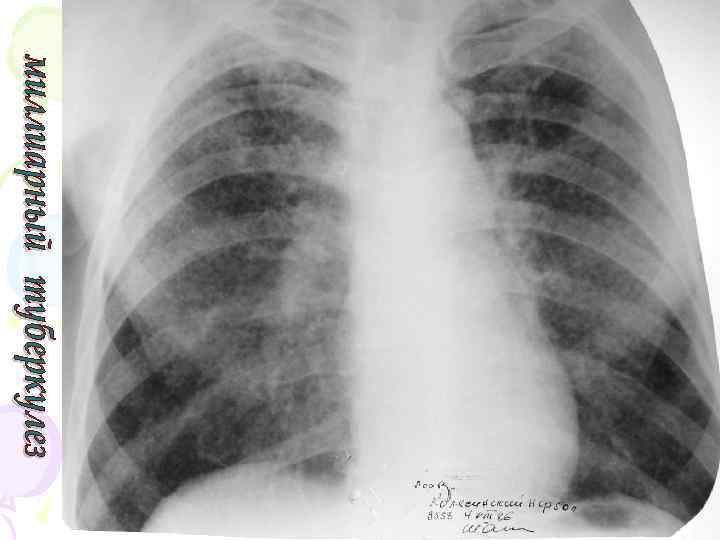

Рентгенологическая картина Спустя 10 -14 дней болезни появляются множественные мелкие / до 2 мм/ однотипные очаги на всем протяжении легких, создается впечатление о более массивной диссеминации в средних отделах. Очаги округлой формы, малой интенсивности, контуры нечеткие, часто расположены в виде цепочки вдоль сосудов. Сосудистый рисунок обеднен